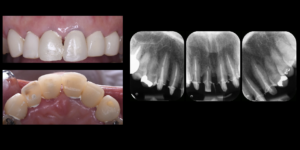

医院ブログ 2026/03/08

【表参道 歯科 ダイレクトボンディング】 破折した... こんにちは。表参道・青山にある歯科石上医院です。 自転車の交通事故…